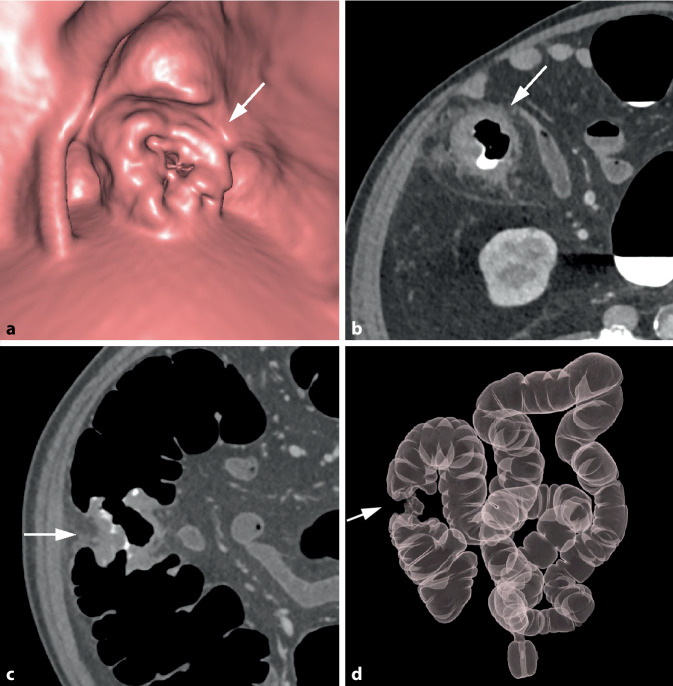

Abstract Image